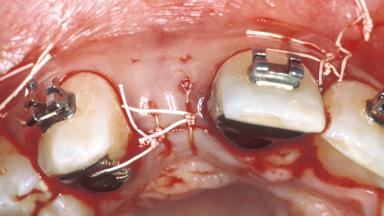

A healthy 32-year-old female patient presented at the clinic for recementation of a resin-retained fixed partial denture (RRFPD) and for a consultation on treatment options to replace the congenitally missing tooth 12. She desired a more esthetic and functional treatment option than her current one. A detailed examination of the teeth and periodontium adjacent to the edentulous space was performed to assess the esthetic risk for implant therapy. The intraoral exam revealed a pre-existing metal-reinforced RRFPD replacing tooth 12. Discoloration of teeth 13 and 11 due to the large metal retainers on the prosthesis was evident.The patient reported several occasions on which the prosthesis had debonded and had to be reinserted. It had become a nuisance for her,and she wanted a more permanent solution. Upon comparison of the adjacent lateral incisors, the mesiodistal width of 12 was slightly smaller and 22 was slightly undercontoured in its incisal embrasure.